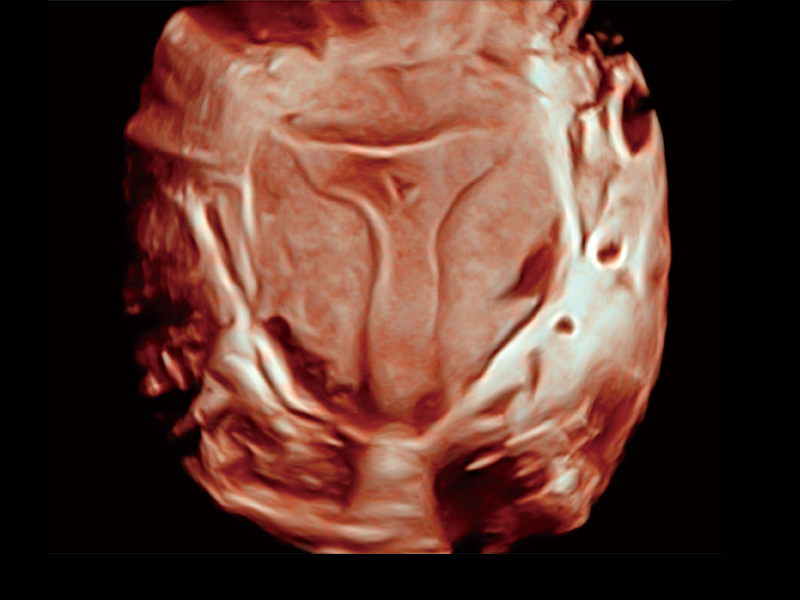

“生育问题”即关系民族复兴,也关系亿万家庭的幸福。随着婚育年龄推迟、社会压力增加等因素,越来越多人群也面临着“生不出、生不好”的问题。辅助生殖作为治疗不孕不育最有效的方法之一,也逐渐成为育儿新希望。而超声检查能为生殖需求人群的初诊评估提供宝贵的信息。 P20 Elite是db真人体育官网匠心打造的一款生殖应用型彩超。她继承db真人体育官网高端极光平台,突破性地将多款新型芯片及硬件模块进行整合,均衡了高端系统性能与小巧灵动机身。P20 Elite卓越的图像质量搭载专科探头,旨在为您提供全面的辅助生殖解决方案。

P20 Elite配备了丰富的生殖探头群和临床应用功能,在卵泡监测、穿刺取卵、胚胎移植、妊娠确认等领域,为生殖需求人群提供了新的临床机会,重新定义高端超声如何应用于生殖健康检查。